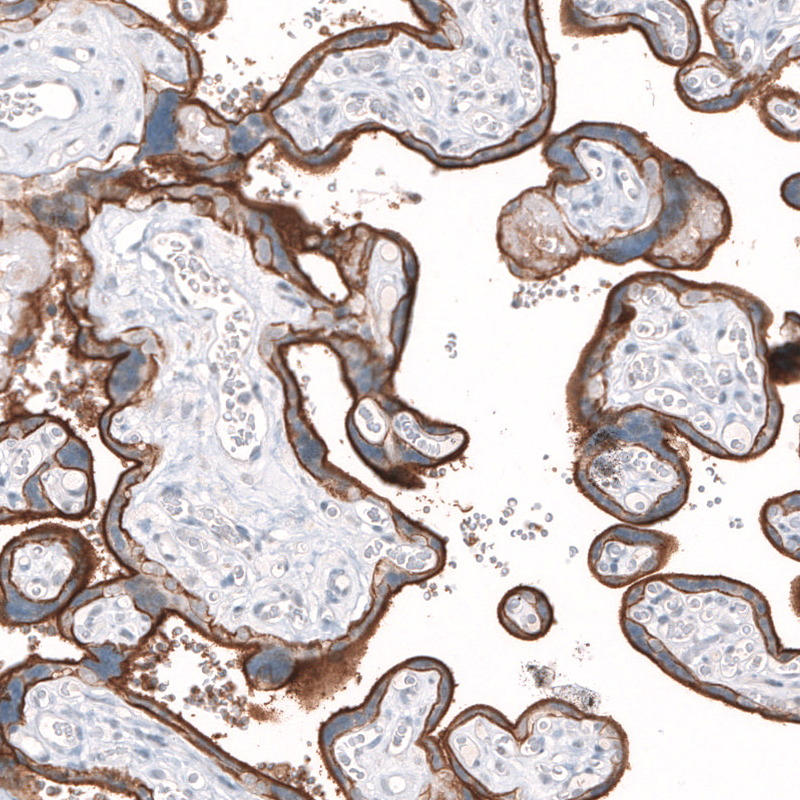

Immunohistochemical staining of human testis shows strong membranous positivity in cells in seminiferous ducts.